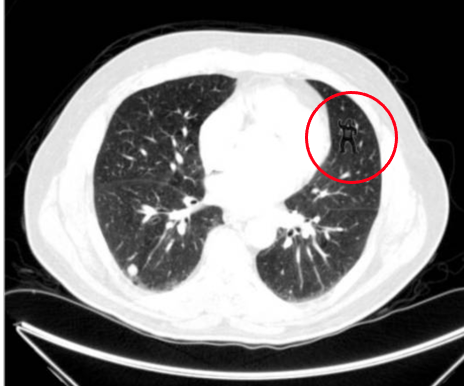

Detta har inte bara visats i hypotetiska scenarier med basketspelare, utan även experter påverkas av inattentional blindness. I en studie visades radiologer, experter i att titta på och utvärdera röntgenplåtar, bilder på lungor och gavs uppgiften att hitta och markera indikatorer på lungcancer. Vad de inte visste var att på vissa av bilderna hade en gorilla lagts in, tydligt synlig för den som visste att den var där. Frågan var om experterna när de granskade bilderna skulle upptäcka gorillan?

Bild från studien med gorillan markerad i övre högra hörnet. Från: Drew T et al. The Invisible Gorilla Strikes Again: Sustained Inattentional Blindness in Expert Observers

Svaret är kanske inte så överraskande, 20 av 24 radiologer såg inte gorillan förrän det blev tillfrågade om de inte såg något ovanligt på bilden. Detta trots att eye-tracking visade att många tittade rakt på gorillan, som var placerad vid indikatorer som deltagarna markerade. Bland icke-experter var resultatet ännu sämre, ingen(!) upptäckte gorillan på någon av bilderna.